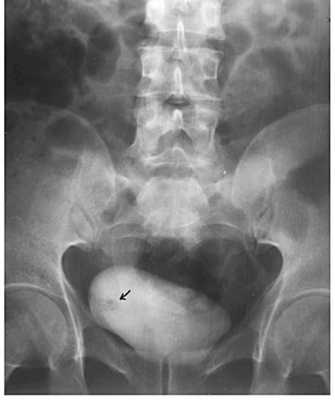

Рисунок. Внутривенная пиелография.

Рисунок. Рентгенологическая диагностика рака мочевого пузыря. При внутривенной урографии выявлен дефект наполнения мочевого пузыря. Это папиллярная опухоль.